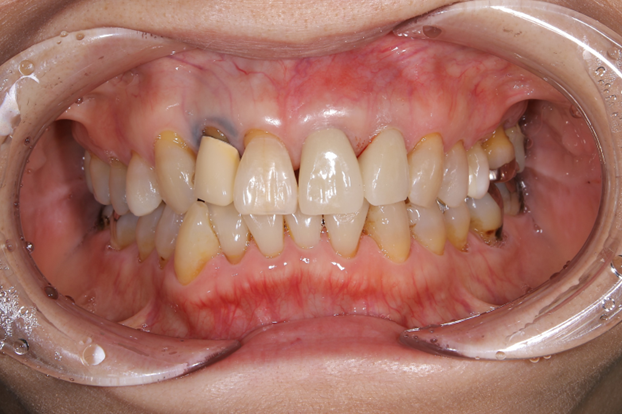

③ジルコニアセラミックを被せて完成

かなり自然な形で歯を修復することが出来たため患者さんにはご満足していただけました。